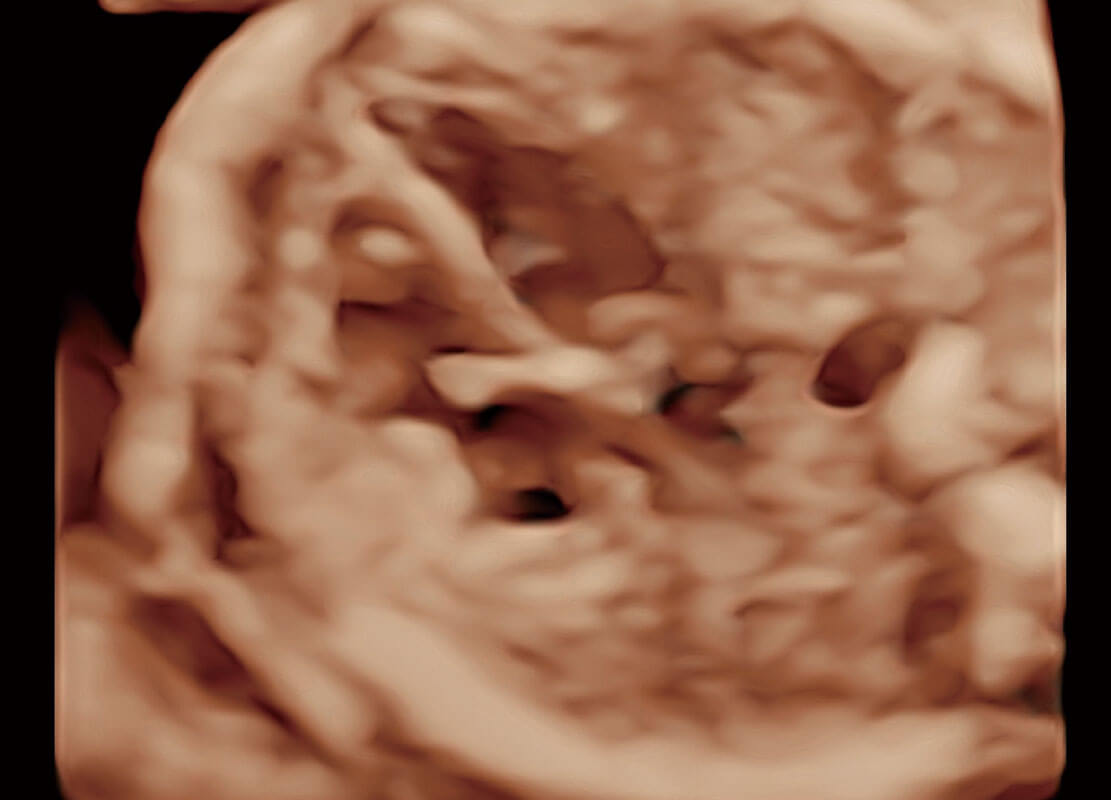

高分辨率容积成像-早孕胎儿

P60在胎儿早孕期超声筛查中为您带来优异的图像质量。